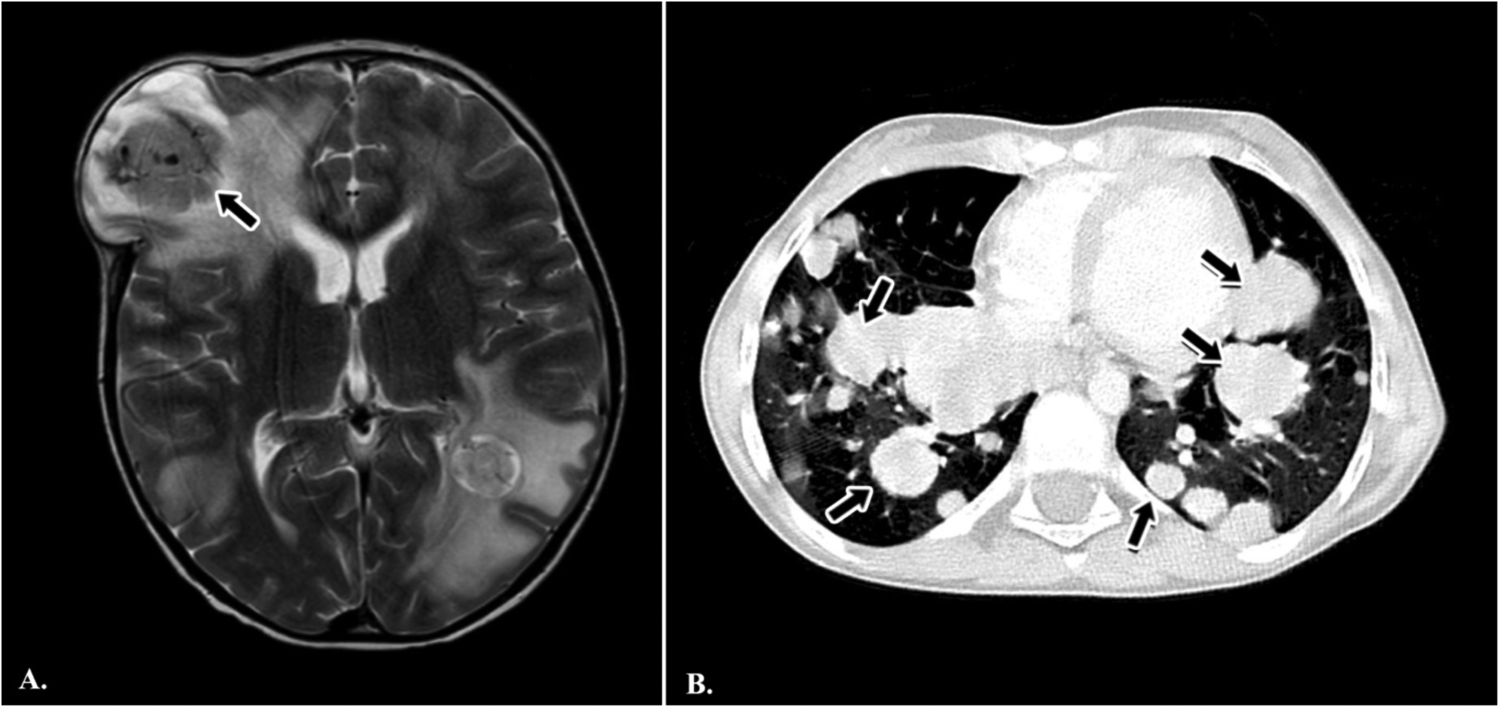

Radiological reassessment demonstrated multiple well-circumscribed pulmonary metastases on thoracic CT and a large left frontal lobe metastasis on brain MRI with surrounding edema (Figures 2A,B). Serial 18F-FDG PET/CT scans performed on 01 July 2022, 24 February 2023, 08 March 2024, and 28 October 2024 revealed a gradual increase in both the number and metabolic activity of pulmonary and mediastinal metastases over time (Figure 3). In addition, PET/CT identified a newly emerging minimally FDG-avid lesion in the distal colon, consistent with intraabdominal metastatic spread (Figure 4). Despite ongoing intensive multimodal therapy, new metastatic foci continued to appear in the mediastinum, colon, and additional pulmonary sites, highlighting the aggressive and refractory course of the disease.

Figure 2. Radiological findings in a pediatric patient with metastatic alveolar soft part sarcoma (ASPS). (A) Axial T2-weighted brain MRI demonstrating a large metastatic mass in the left frontal lobe with surrounding edema (black arrow). (B) Axial chest CT scan showing multiple, bilateral, well-circumscribed pulmonary metastases of varying sizes (black arrows).